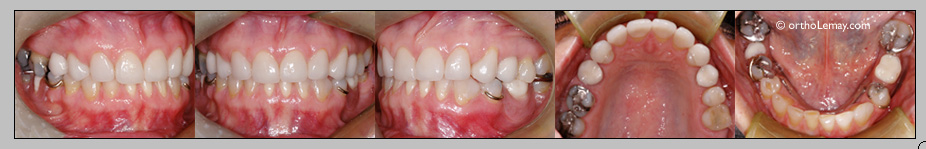

Le cas MC: après l’orthodontie

Un an après l’orthodontie, les restaurations finales sont en place; facettes sur plusieurs dents supérieures, les couronnes sur implants sont posées et une prothèse partielle amovible remplace les dents manquantes inférieures.